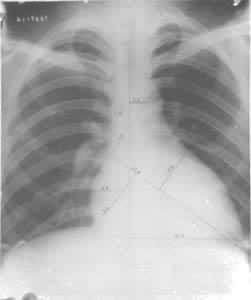

运动员尸检材料发现运动训练可引起明显的心肌肥厚放射线检查可见运动员心脏面积和容积增大。心面积增大者以耐力训练项目运动员为最多(图1)。心面积增大的程度,多数不超过其预测面积的30%。运动员心脏容积一般也较大,中国正常成人心脏容积最大为870.68ml,中国运动员心脏容积最大者为1209.45ml,其心脏面积也最大(为+55.32%)。外国文献报道,职业自行车运动员和水球运动员心脏容积最大可达1700ml。训练内容不同对心脏的影响也有差别,耐力训练运动员的心脏以心腔扩张为主,力量练习运动员的心肌肥厚可稍占优势。

运动员心脏放射线检查